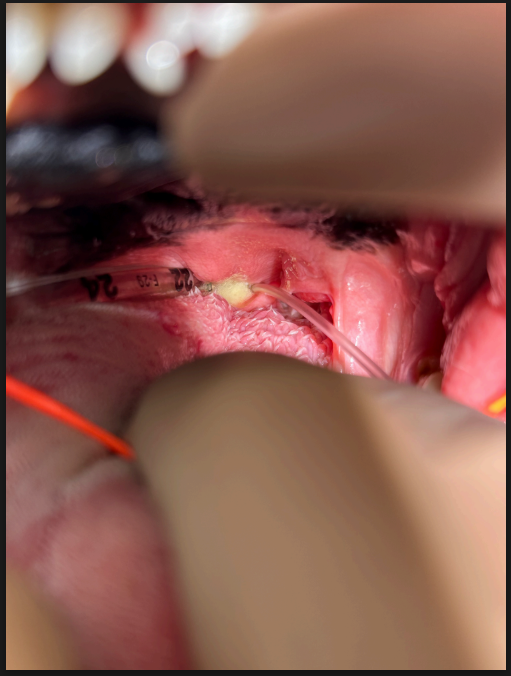

▼軟口蓋手術後:軟口蓋切除後